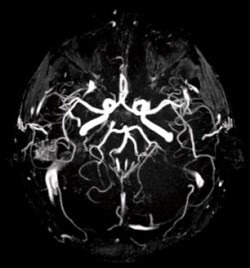

Az angiográfia az agyi erek (MRI) ár Moszkvában

Angiographiás MRI hajók jelentős különbség van. A módszer elvét teljesen más - a hatása erős elektromágneses mező, így a kontrasztanyag használt egyéb - alapján sók a gadolínium. Mindkét módszer egyformán tájékoztató megvizsgálni az agyi erek.

- MRI angiográfia;